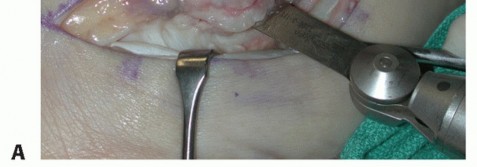

| We use a standard lateral incision along the course of the peroneal tendons, taking care not to injure the sural nerve. | |||

| Carry the incision down to the level of the peroneal tendon sheath (TECH FIG 1A). | |||

TECH FIG 1 • A. Intraoperative photograph of a left ankle (lateral approach) shows the peroneal tendons subluxing anteriorly (brevis is the gray arrowhead , longus is the white arrowhead , SPR is the black arrow). B. The peroneal tendons have been retracted anteriorly by the Penrose drain. Elevation of an anterior-based periosteal flap (outlined by dots) from the fibular groove has been completed. The black arrow shows the remnant of the SPR posteriorly. C. The tendons are relocated, after a groove-deepening procedure, into the recreated groove. The white dots outline the anteriorly based periosteal flap. It is then brought over to the posterior remnant of the SPR (black arrow). D. The flap is sutured to the remnant SPR with nonabsorbable sutures, completing the superior peroneal retinaculoplasty. |

| Inspect the SPR. Usually, it is attenuated and deficient, especially along its anterior border. The retinaculum often is lifted off its fibular attachment, thus allowing the peroneal tendons to subluxate. | |||

| Make an incision in the peroneal sheath along the posterior border of the fibula. Retract the peroneal tendons anteriorly (TECH FIG 1B). | |||